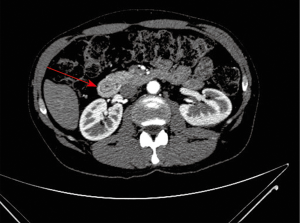

A 46-year-old Caucasian male with a smoking index of 30 pack-years and chronic alcohol consumption of 160 grams per day, with no history of past medical conditions, and with a family history of pancreatic and gastric cancer, presented to the emergency unit with a 6-month history of intermittent colicky epigastric pain irradiated to both hypochondria and back, with a progressive increase in intensity that worsened with food intake causing a limitation to food ingestion that lead to asthenia and loss of 20 kg. of weight in the previous 6 months. He also described post-prandial fullness, nausea and a change in bowel habits for the last 5 months in the form of progressive constipation for which he underwent colonoscopy 3 months prior to his presentation that only revealed a sessile polyp in the descending colon without histological abnormalities. He denied vomiting, hematemesis, hematochezia or melena. On examination he was normotensive, afebrile, with normal rubor. Abdominal examination revealed tenderness in epigastrium and both hypochondria with abdominal guarding, and normal bowel sounds. No masses were palpated. Proton pump inhibitors, gastroprokinetic agents and analgesia with acetaminophen and metamizole didn’t alleviate his symptoms. Laboratory tests revealed normal leukocyte count, acute phase reactants, liver and pancreatic enzymes. Abdominal X-ray showed no abnormalities, and he was admitted to hospital for further study, undergoing upper gastrointestinal endoscopy that revealed grade I oesophageal varices, mild hiatal hernia and chronic antral gastropathy. Abdominal ultrasonography revealed a small hepatic hemangioma with homogenous hepatic parenchyma, and no biliary, pancreatic or splenic anomalies. After progression of the severity of symptoms further study was followed with computerized tomographic enterography that revealed a band of pancreatic parenchyma surrounding the descending portion of the duodenum, with the pancreatic duct opening in the duodenum anterior and superior to the biliary duct opening (Figure 1). Barium meal was done that revealed an extrinsic compressing effect on the descending part of the duodenum without obstruction, proximal dilatation or gastric retention (Figure 2). Conservative treatment with analgesics, soft diet, proton pump inhibitors and gastroprokinetic agents was decided at first considering that the patient didn’t show duodenal obstruction or any other complication, with failure to control the symptoms. Due to failure of conservative treatment and high risk of the patient to develop complications (chronic smoker and heavy alcohol consumer, family history) surgical approach was decided. Laparoscopic duodenojejunostomy was performed with no post-operative complications. No enlarged lymph nodes were detected in the periportal or peripancreatic regions. Relief of symptoms was achieved after 48 hours of the procedure. The patient had an improved appetite with progressive gain of weight in the following year of follow-up.